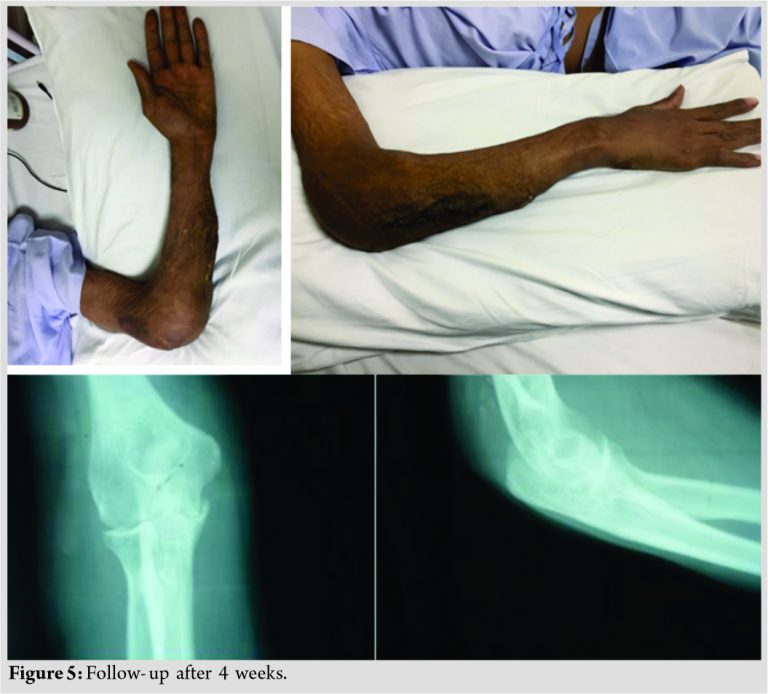

The microbiological and histopathological examination of the synovial and necrotic tissue showed caseating granulomas with cells is as Langhans giant consistent with tuberculosis. Postoperatively, the patient was put on antitubercular drugs which included four agent drug treatment using isoniazid, rifampicin, pyrazinamide, and ethambutol (AKT-4). On follow-up at 4 weeks and 3 months, thereafter the swelling did not recur (Fig. 5).

At present, he is improving with no recurrence of swelling.